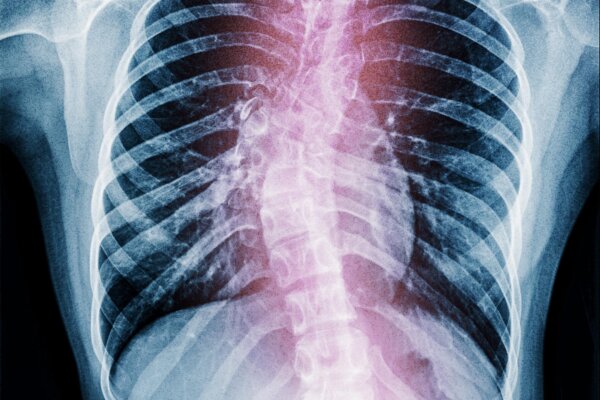

If you’ve been battling unexplained lower back pain, uneven shoulders, or an increasingly unsteady gait, your body may be signaling a deeper structural problem: your spine could be drifting out of alignment. Many people dismiss these subtle symptoms, yet experts warn that scoliosis often progresses quietly—sometimes until breathing becomes difficult or nerve function is compromised.